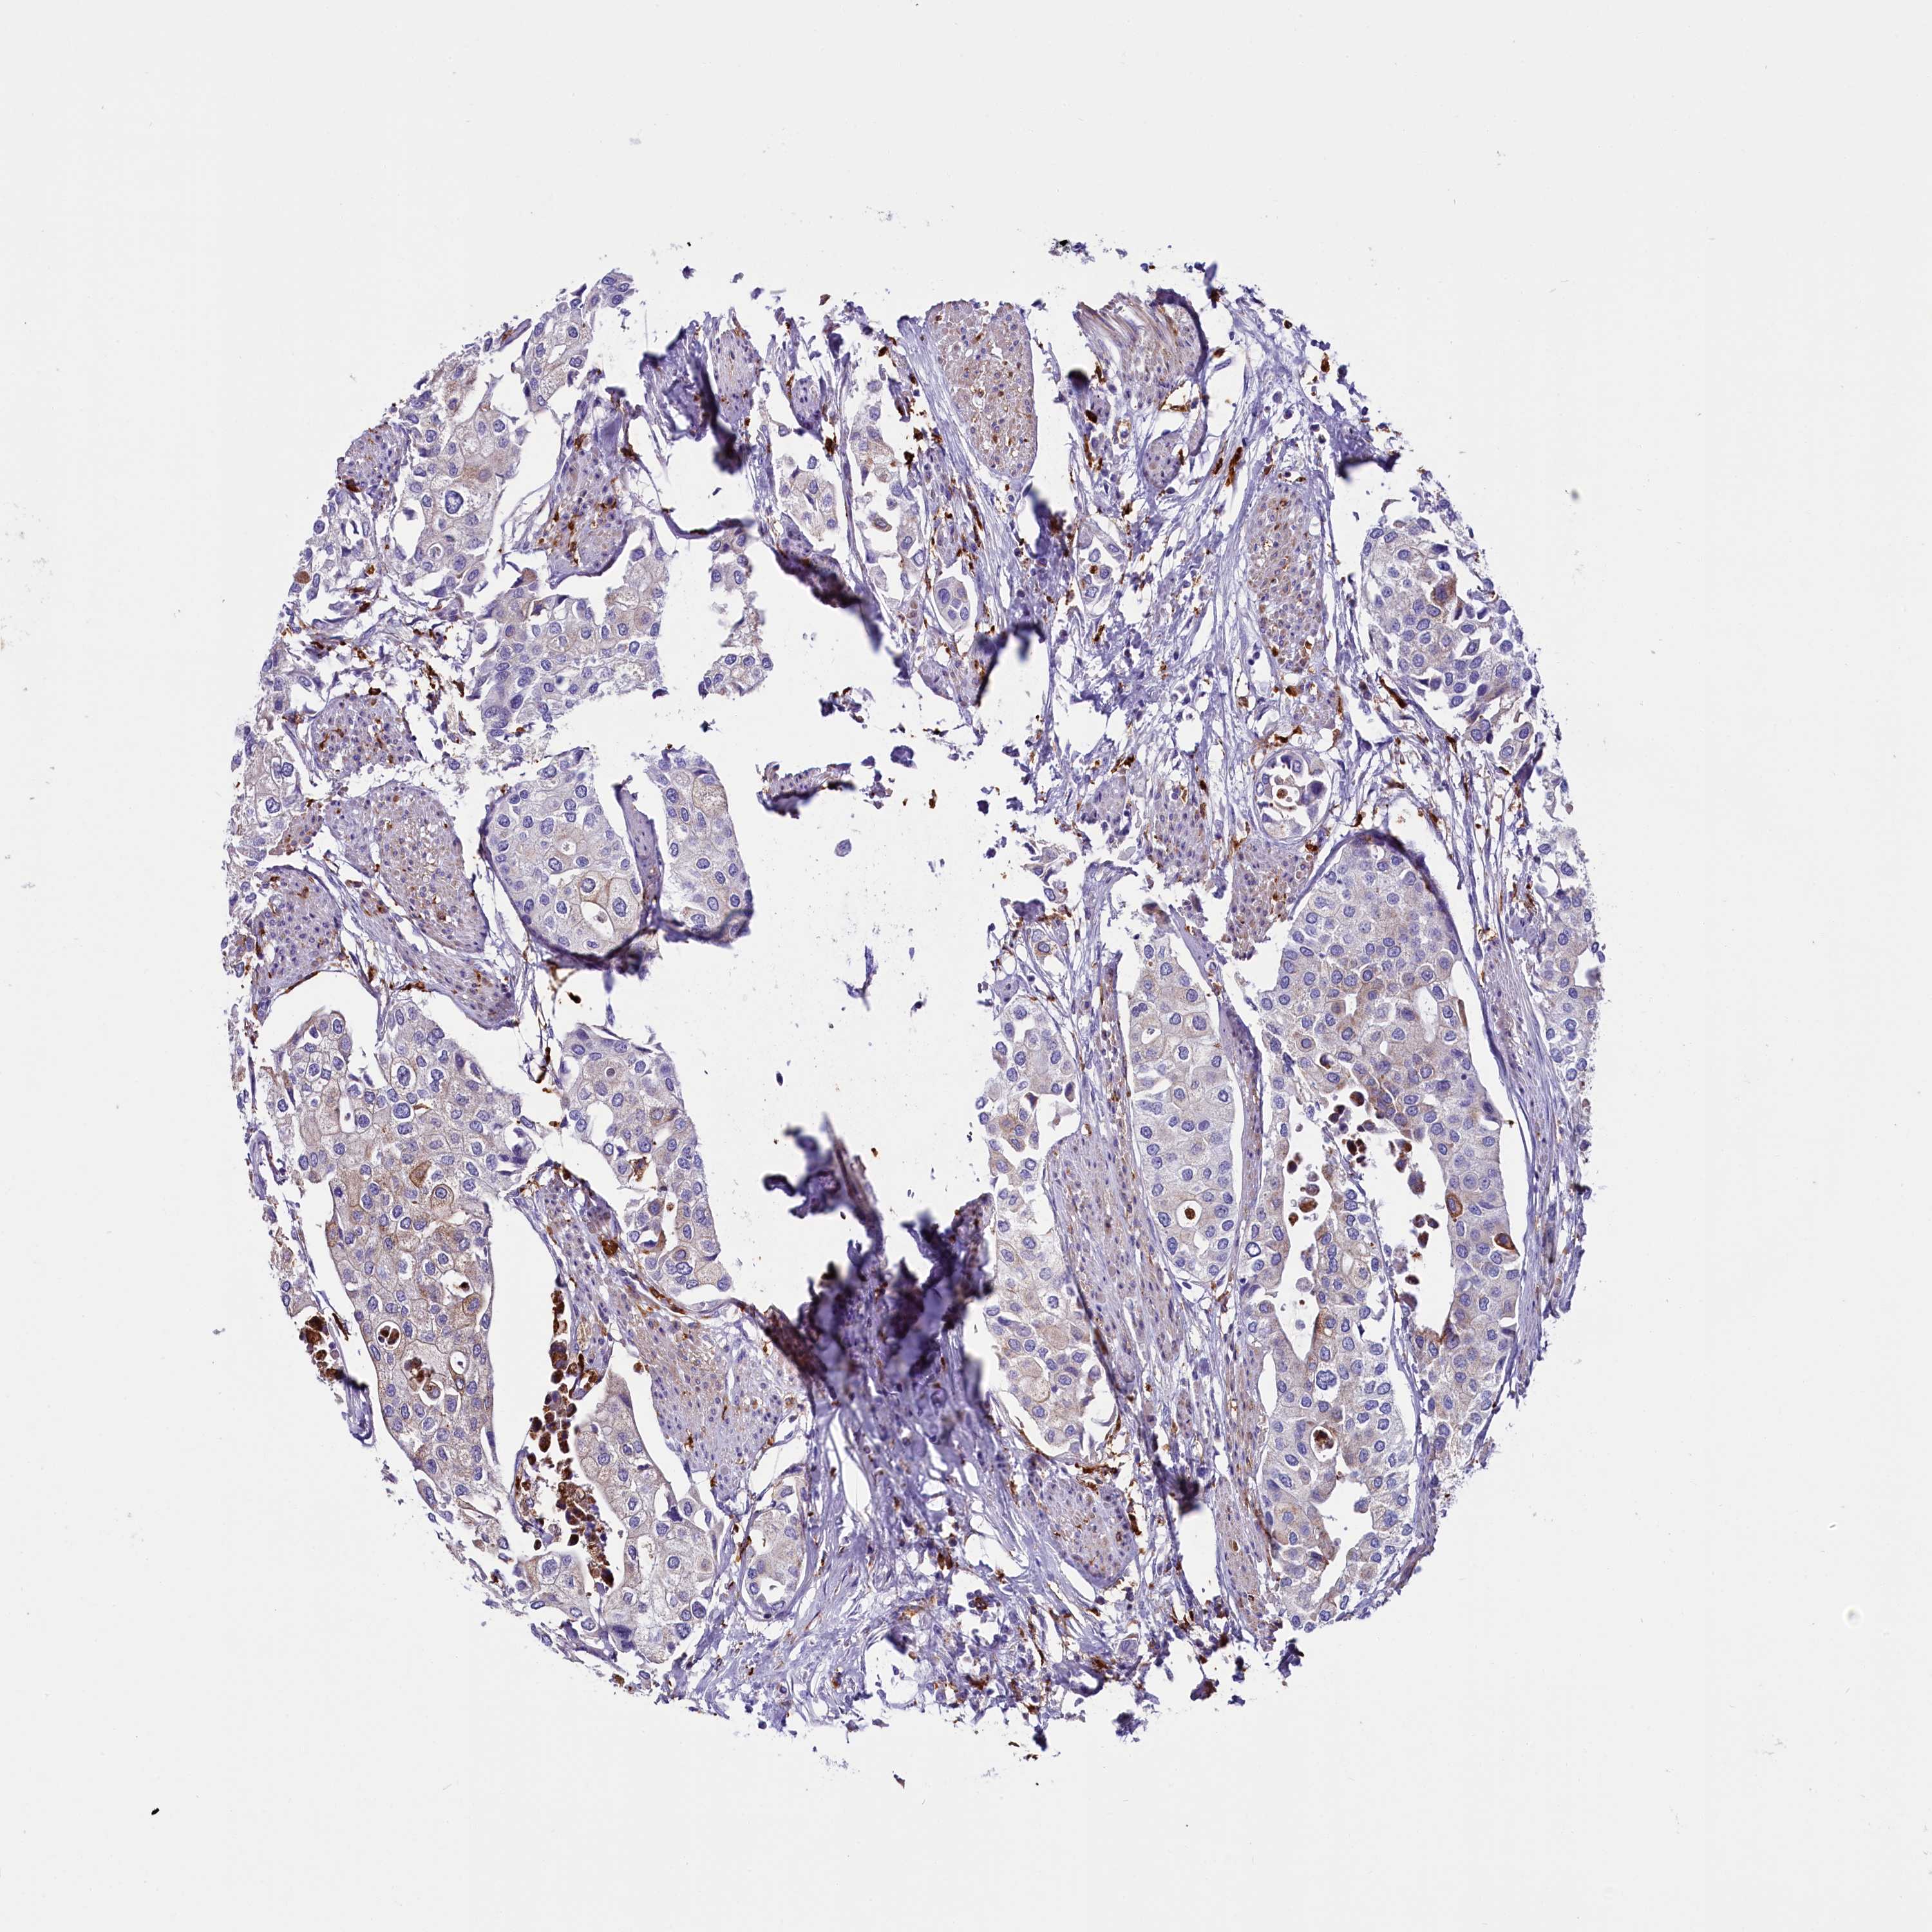

UROTHELIAL CANCER - Protein expressioni

A mouse-over function shows sample information and annotation data. Click on an image to view it in a full screen mode. Samples can be filtered based on level of antibody staining by selecting one or several of the following categories: high, medium, low and not detected. The assay and annotation is described here.

Note that samples used for immunohistochemistry by the Human Protein Atlas do not correspond to samples in the TCGA dataset.

Antibody stainingi

Antibody staining in the annotated cell types in the current human tissue is reported as not detected, low, medium, or high, based on conventional immunohistochemistry profiling in selected tissues. This score is based on the combination of the staining intensity and fraction of stained cells.

Each image is clickable and will lead to virtual microscopy that enables deeper exploration of all samples and also displays staining intensity scores, fraction scores and subcellular localization as well as patient and tissue information for each sample.

Antibody HPA042281

Antibody CAB024990

Urothelial carcinoma, High grade

Urothelial carcinoma, Low grade